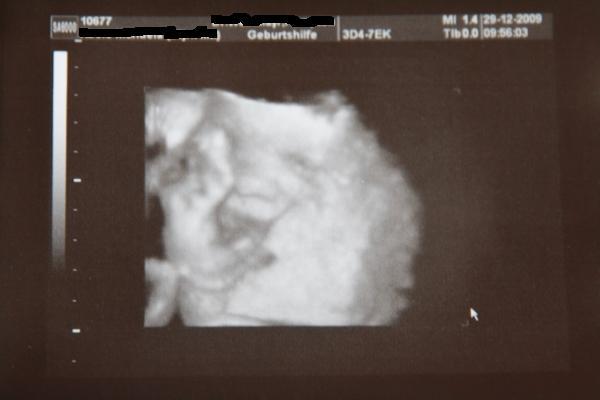

Hallo Mädels, war heute morgen beim Doc, alles super. Baby gehts gut, ist alles zeitgerecht entwickelt (SSW 28+6). Die Daten: BPD 7,4 FOD/KU 9,5 ATD 6,9 APD/AU 22,3 FL/HL 5,6 Es ist immer noch ein Mädchen (muss jedesmal nachfragen) Beim CTG waren auch keine Auffälligkeiten zu sehen... Endlich hat das mit dem 3D mal geklappt, ich hoffe ihr könnt was erkennen, finde sie total süß vlg Manu

Bild zu Heutige VU.... mit 3D - Forum für März - Mamis